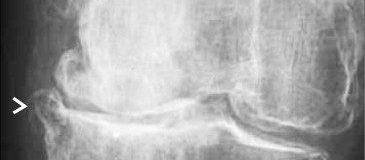

The management of chondral disease poses challenges due to its poor healing potential. Biomechanical and biological changes can accelerate degeneration, leading to end-stage osteoarthritis (OA).

The study, approved by the Ethics Committee, involved 30 patients with diffuse degenerative chondral lesions treated with autologous micro-fragmented adipose tissue between January and December 2014. Clinical evaluations were conducted at 3 years post-treatment.

The study demonstrates sustained benefits of autologous micro-fragmented adipose tissue in treating diffuse degenerative knee chondral lesions at mid-term follow-up, supporting its role as an adjunct in surgical procedures.